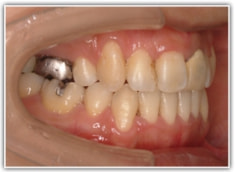

治療前

修復歯、補綴歯もあります。下顎8番が水平埋伏しています。